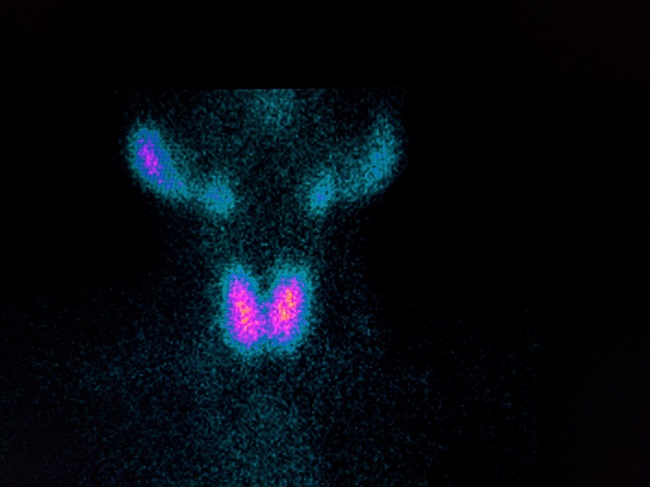

Gambar 1. Gambaran Graves’ Disease

- Gambaran khas sidik tiroid untuk Graves’ disease adalah distribusi aktivitas tinggi difus homogen di kedua lobi tiroid dengan berkurangnya distribusi aktivitas pada kelenjar saliva mayor, dan latar belakang/background

Gambaran sidik tiroid normal akan menunjukan distribusi aktivitas homogen dari kelenjar tiroid berbentuk seperti kupu–kupu. Visualisasi isthmus tiroid bervariasi pada pasien.

Lobus piramidalis biasanya tidak terlihat pada pasien normal. Jika terlihat terletak di anterior dan superior isthmus tiroid. Distribusi aktivitas fisiologis dapat terlihat pada kelenjar parotis bilateral dan kelenjar saliva submandibular bilateral dengan intensitas yang lebih rendah dibandingkan kelenjar tiroid.[1–3]